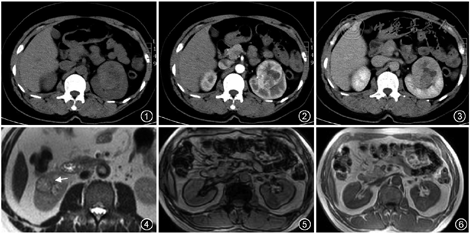

肾透明细胞癌的CT平扫可为等、稍高或稍低密度(图1)。在MRI上,透明细胞癌通常在T1WI上呈等、低信号,在T2WI上呈高信号,DWI上呈较明显的扩散受限改变[3]。透明细胞癌增强的典型特征是肾皮质期的明显不均匀强化[4](图2),有“速升速降”的增强特点。增强皮质期多与肾皮质的高强化相似,故较小病变于肾皮质期可能因为肾皮质本身的高强化而显示不明显,反而于肾实质期因肾实质本身的均匀高强化使得病变显示更清晰(图3)。部分肿瘤可有假包膜,主要为周围的纤维性包膜以及被挤压的肾实质,在T2WI上呈低信号环(图4)。约80%的透明细胞癌有细胞内脂质或脂肪变性,从而导致反相位图像的信号强度较同相位图像信号减低[4](图5,6)。